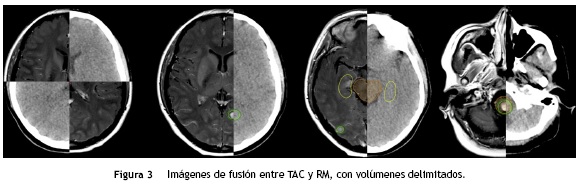

A continuación se presenta una serie de imágenes en las que se compara la calidad de la imagen en la TAC de simulación con la resonancia magnética. Posteriormente, se presentan las imágenes de la fusión realizada y los volúmenes de delimitación. Por último, se muestran las imágenes de dosimetría en las cuales es posible apreciar la diferencia de dosis administrada a las lesiones y a los órganos sanos a riesgo.

En la figura 3 se presentan las imágenes de la fusión entre la TAC y la RM. Mediante el sistema Eclipse® la fusión automática inicial se realiza identificando estructuras o densidades similares visibles en ambas imágenes y, posteriormente, se realiza un ajuste fino de forma manual de la posición de las imágenes hasta coincidir la ubicación de las estructuras de la RM sobre la TAC de simulación. Se observa que ha sido posible realizar la delimitación de las lesiones metastásicas con alta precisión, así como de los hipocampos y otras estructuras a riesgo, en este caso, el tallo cerebral.

Mediante la fusión de imágenes (TAC y RM) fue posible observar la ubicación precisa de las metástasis cerebrales y realizar la delimitación del volumen del hipocampo con mayor exactitud de la que se hubiera conseguido en caso de contar únicamente con imágenes de TAC de simulación, las cuales ofrecen una baja resolución y rendimiento para la delimitación de volúmenes en tejido nervioso. Gracias a los nuevos algoritmos de fusión de imágenes en los software de radioterapia no es necesario que la posición en la que se toma la imagen de RM sea igual a la posición en la que se toma la TAC de simulación, ya que estos algoritmos utilizan información de ambas series igualando diversas características estructurales de las imágenes mediante herramientas de rotación y traslación. Esto representa una ventaja para la planeación del tratamiento, ya que es posible utilizar imágenes de RM que han sido tomadas previamente, disminuyendo los gastos y tiempo transcurrido en los que se incurriría si fuese necesario adquirir un nuevo set de imágenes.